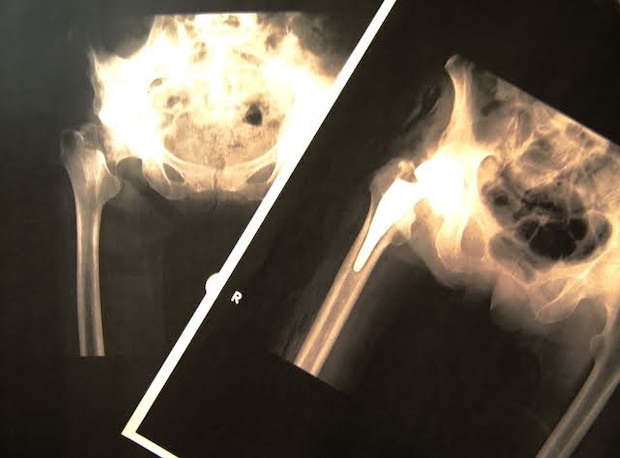

骨嚢腫(こつのうしゅ)とは、骨の内部に嚢胞(のうほう:袋状の空胞)ができる病気です。骨嚢胞(こつのうほう)と呼ばれる良性腫瘍に似ています。

上腕骨(腕の骨)と大腿骨近位端(ふとももの骨の股関節側)にできやすく、病的骨折の原因になります。女性よりも男性に多い病気で、小児から若年者に好発します。また、骨の成長とともに病巣が骨の端から骨幹部(骨の中心)に向かって移動する特徴があります。

骨嚢腫の原因として、外傷による骨髄内出血や炎症、骨髄内に残された滑膜組織、静脈の血流障害が挙げられます。骨嚢腫は発症しても問題ない経過をたどることが多いですが、病的骨折や痛みを伴う場合には手術が選択されます。また、子どもで骨端線(こったんせん:骨が成長する部位)に近い箇所に骨嚢腫ができた場合は再発率が高いため注意が必要です。骨嚢腫の再発が繰り返されると、骨の変形につながる可能性があります。